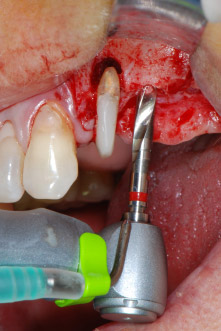

Имплантологичното ложе е подготвено в позиции 25 и 26 с ротиращи инструменти, използвайки обратен наконечник 20:1 с усъвършенстван и мощен имплантологичен мотор (Implantmed, W&H) (Фиг. 8).

Следващата препарация близо до синуса отново е извършена с пиезохирургичен накрайник (Piezomed, накрайник S2).